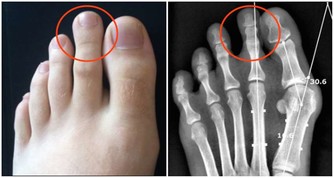

現在的醫療發展已經可以治療相當多的疾病,也儘管還有許多疾病無法治愈,但可以依靠藥物和其他治療方法延緩進展。不過,這些療法和治療效果有一個共同特點:越早診斷和開始治療效果越好,所以體檢發現的疾病萌芽,往往可以在發病初期被治愈或者控制,哪怕是癌症。等到了有症狀再去看醫生,很多疾病實際上已經進入末期了。